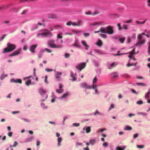

onset of a nodule, with development of ulceration . However, some acral melanomas may be deeply invasive while remaining quite flat because the thick stratum corneum seems to act as a barrier to exophytic growth. Histopathology. The lesions are termed lentiginous because the majority of the lesional cells are single and located near the dermal-epidermal junction, especially at the periphery of the lesion . However, usually some tumor cells can be found in the upper layers of the epidermis, especially near areas of invasion in the center of the lesions. The histologic picture differs from that of lentigo maligna because of irregular acanthosis, the lack of elastosis in the dermis, and the frequently dendritic character of the lesional cells . Early in situ or microinvasive lesions may show, especially at the periphery, a deceptively subtle histologic picture consisting of an increase in basal melanocytes and hyperpigmentation with only focal atypia of the melanocytes. However, in the center of the lesions, there is usually readily evident uniform, severe cytologic atypia. There may be a lichenoid lymphocytic infiltrate that may largely obscure the dermal-epidermal junction, and in some cases this may be so dense as to simulate an inflammatory process. In most of the lesions, both spindle shaped and rounded, pagetoid tumor cells are seen, and, in many cases, pigmented dendritic cells are prominent. Pigmentation is often pronounced, resulting in the presence of melanophages in the upper dermis and of large aggregates of melanin in the broad stratum comeum. As in lentigo maligna, when tumorigenic vertical growth phase is present, it is often of the spindle cell type and not uncommonly desmoplastic and/or neurotropic. In |